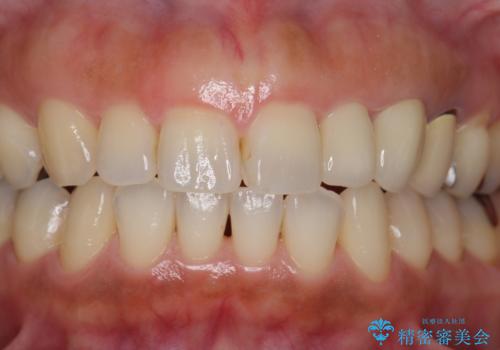

前歯が左右対称じゃない 保険の被せ物をきれいにしたい ホワイトニング併用

- 左上の前歯が小さく左右対称ではないのと、保険の前歯の被せ物のやりかえを希望して来院。

小さい前歯は、反対側と合わせた形にしました。

左右対称に仕上げることができ、治療には非常に満足していただきました。